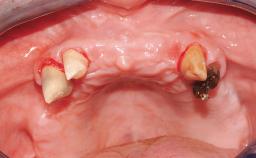

In this video Dr. Legg will demonstrate the process of utilising fully guided surgery as well as reconstruction to provide immediate full arch rehabilitation. A 56-year-old female with chronic adult periodontitis had previously undergone significant nonsurgical periodontal therapy. Unfortunately she had reached the stage where she was no longer happy with the appearance of her teeth and was suffering from increasing discomfort. A full workup was carried out in conjunction with a technical design team (at Createch). This included digital wax up of the proposed teeth, digital placement of the proposed implants and the design of the requisite surgical guides. The surgery was then carried out under sedation. The remaining upper teeth were removed, bone reduced where appropriate and the implants placed using a fully guided protocol. Following placement of screw retained abutments, the immediate provisional prosthesis was picked up in situ and passed to the technician for finishing before being fitted.